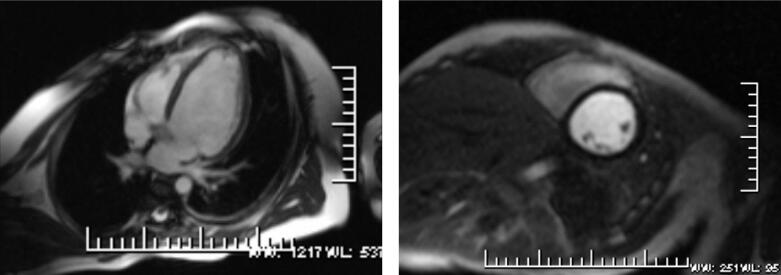

磁共振成像参数应用1.5T场强的MRI仪(Magnetom Sonata,Siemens),患者取仰卧位,头先进,32通道心脏表面线圈,心电门控,采用黑血脉冲序列获得体轴横断位图像,然后行四腔心、两腔心长轴和两腔心短横断位梯度回波电影、静息态心肌灌注采用两腔心短轴和四腔心层面,应用钆喷酸葡胺对比剂,按0.2mmol/kg体重注射。灌注扫描的对比剂流率为5ml/s,总量8ml。延迟强化扫描注射对比剂的流率为2ml/s,总量14ml。通常在心肌灌注扫描后8~10分钟进行延迟扫描。整个心脏MRI检查方案见表1。影像学检查见图1。

图1 冠状动脉左主干起源于右窦

冠状动脉CTA:左主干起自右窦,走形于右室流出道与主动脉之间,前降支走形于前室间沟;管壁规则,左主干管腔受压,余前降支管腔通畅,未见明显狭窄或扩张改变。

MRI表现:心内结构未见明显异常,左室增大;心脏电影显示左室前壁、侧壁及心尖节段运动减低,各瓣膜收缩舒张未见明显异常,未见返流信号;心肌静息灌注显像见左室前壁、侧壁及心尖心内膜下灌注减低,心肌延迟强化序列显示对应节段延迟强化。